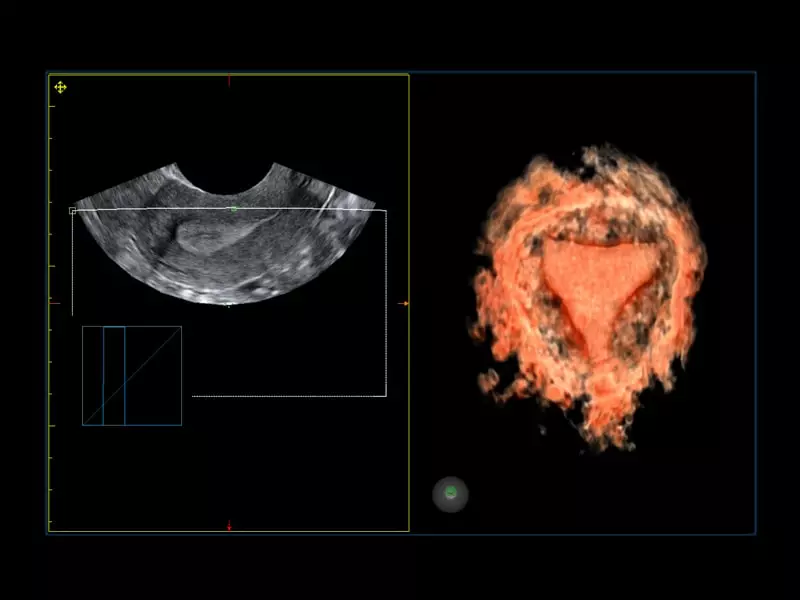

MyLab™C30 - Gyn 3D

MyLab™C30 - Gyn 3D

MyLab™X1 Go - WH Endometrium

MyLab™X1 Go - WH Endometrium

MyLab™X1 Go - Gyn

MyLab™X1 Go - Gyn

MyLab™Omega - IUD visualization using 3D endocavitary probe

MyLab™Omega - IUD visualization using 3D endocavitary probe

MyLab™A50 - Uterus

MyLab™A50 - Uterus